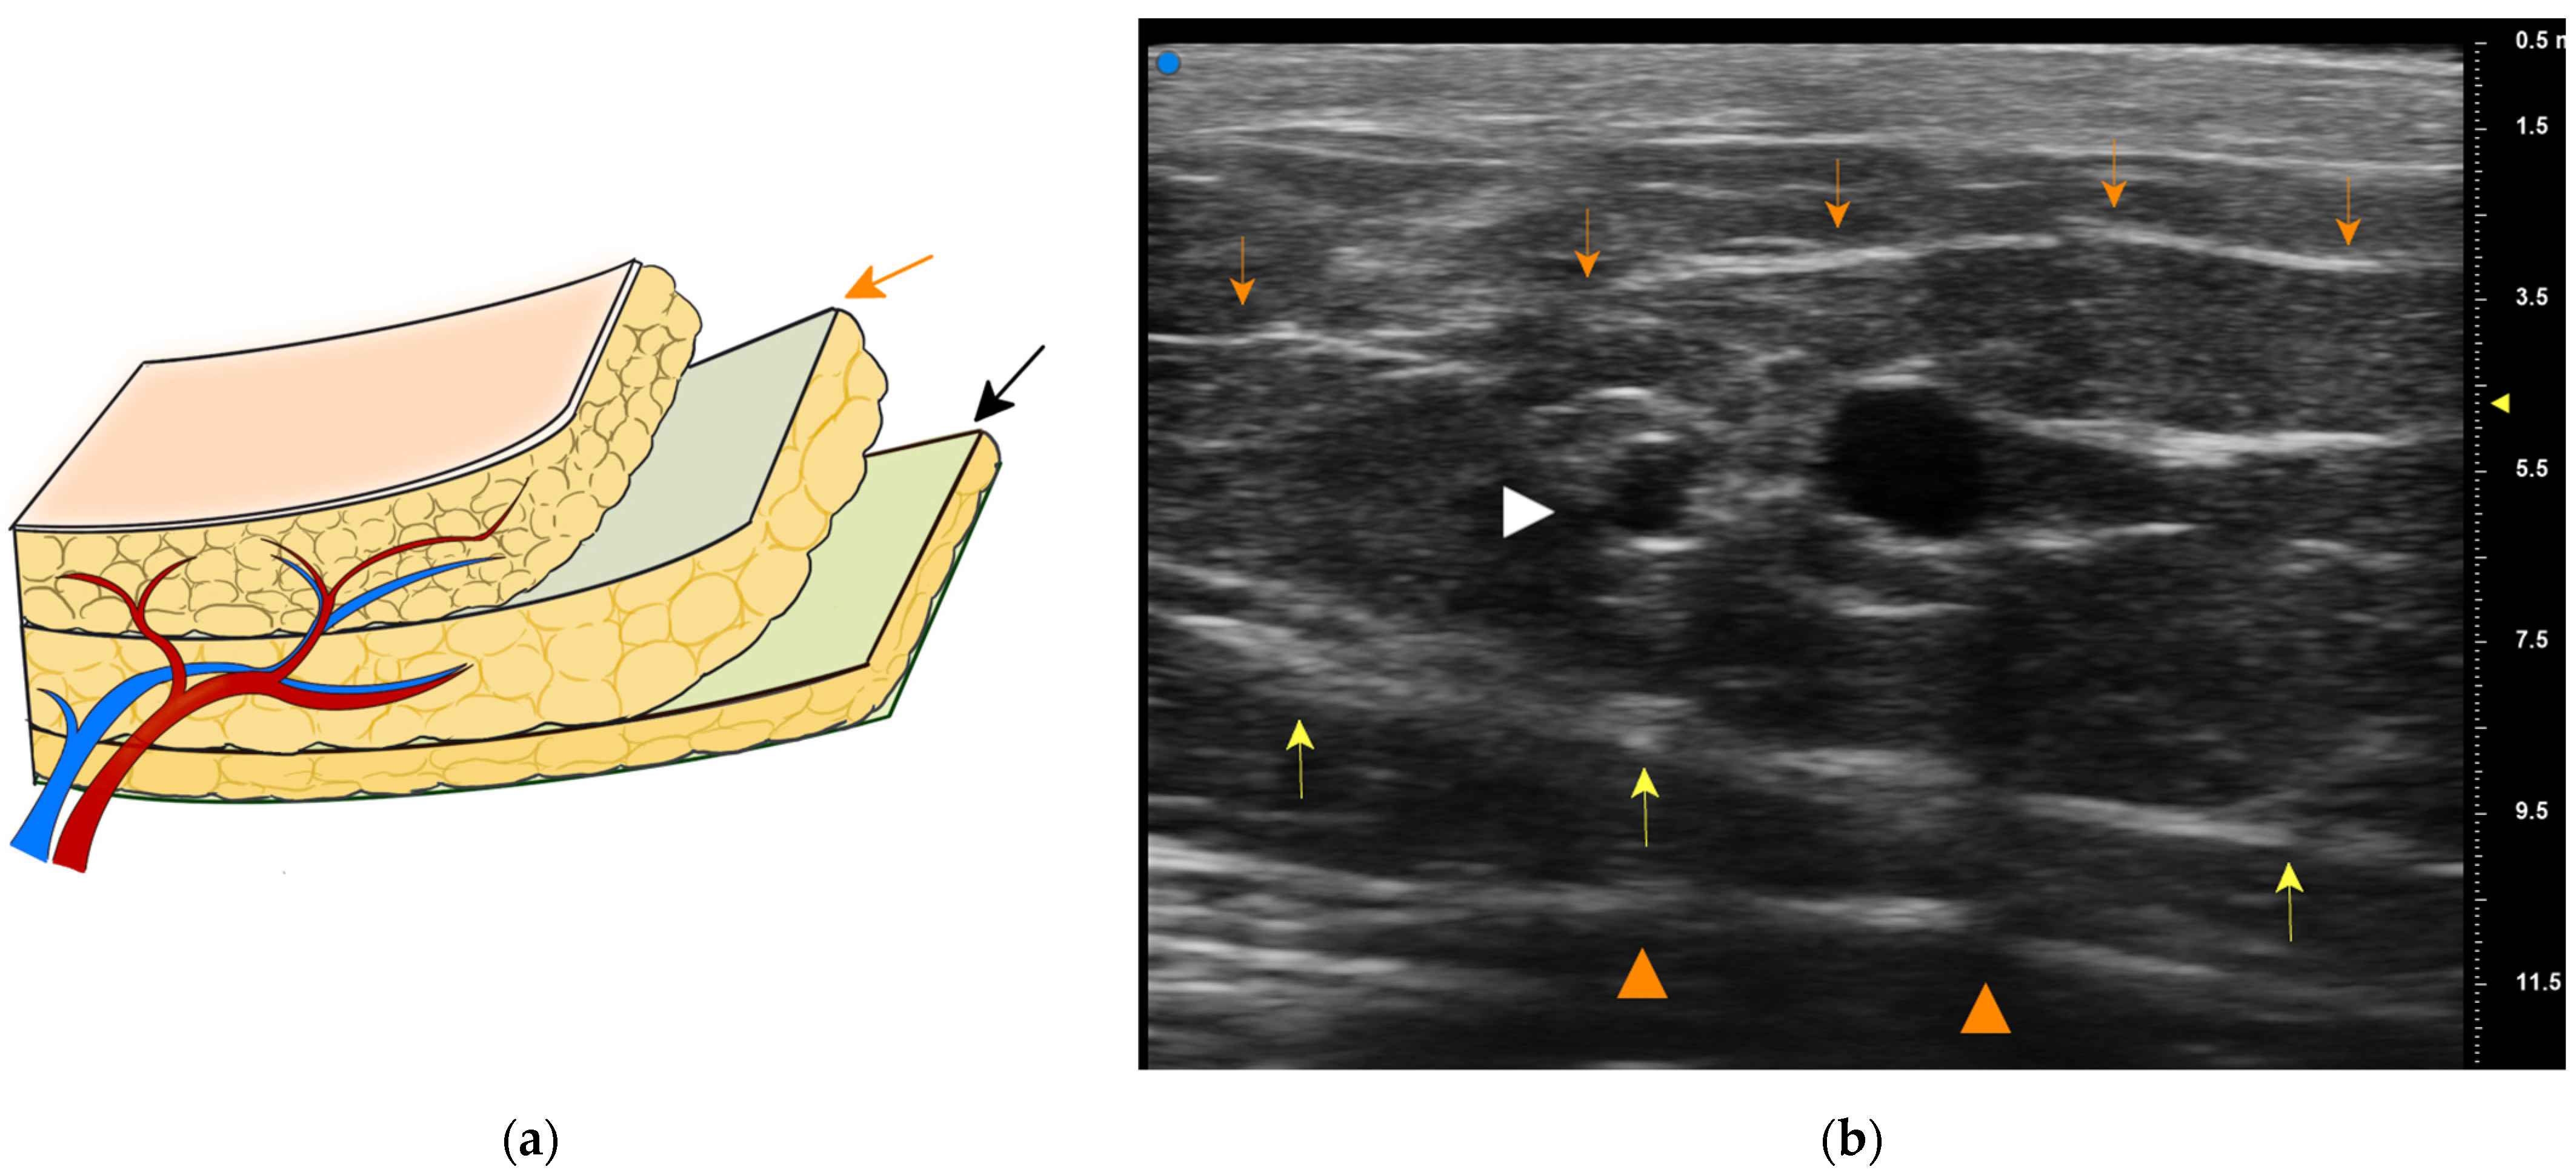

We routinely employ elevation in a proximal-to-distal fashion [9]. A superficial branch of the SCIA is first identified in the proximal region, which is usually between the superficial and the Camper fasciae (Figure 7). The pedicle is rather large and easy to be found with an aid of high-resolution ultrasonography [16]. We then make a circumferential skin incision and dissect toward the Camper fascia. Thus, the pedicle above the Camper fascia is included safely. Furthermore, most of the pedicle is covered by the fat between two fasciae (Figure 3b), contributing to safer transplant with a less possibility of kinking of the pedicle.

Figure 7.

(a) Showing two distinct planes: the superficial fascia (orange arrow) and the Camper fascia (black arrow). (b) High-resolution ultrasonographic imaging of the SCIA superficial branch. The superficial branch (white arrow head) is identified between the superficial fascia (orange arrows) and the Camper fascia (yellow arrows). The Scarpa fascia is also distinct (orange arrow heads).